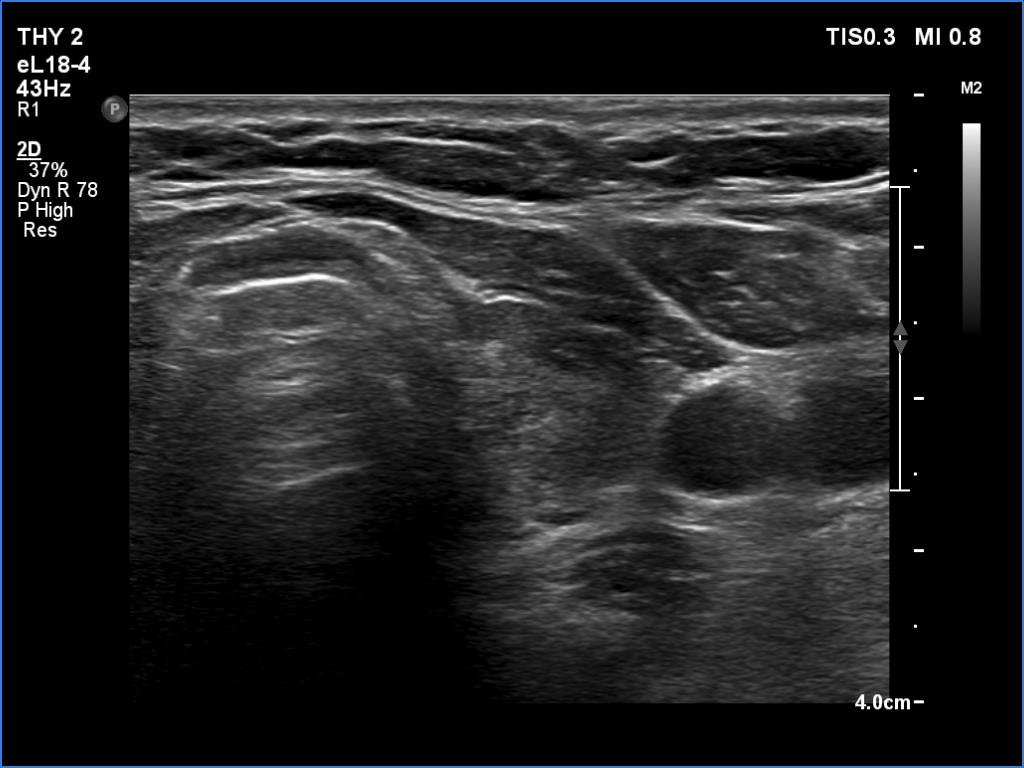

The operated thyroid - case 1388

Five years after the surgery (ultrasonographic picture 4)

Right lobe, longitudinal scan

Lower part of the left lobe, transverse scan. Here, the pattern is more inhomogeneous.